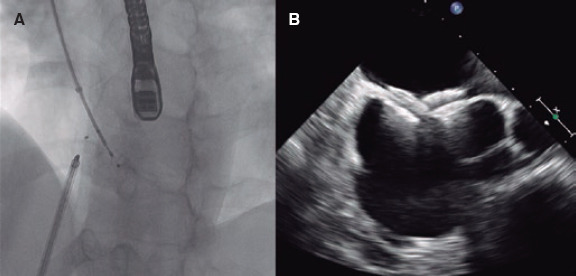

Introduction and objectives: Multi-fenestrated atrial septal defects (mASD) pose both diagnostic and therapeutic challenges. This study aimed to compare the outcomes of transcatheter closure in patients with mASD vs those with a single ASD at our center.

Methods: We conducted a retrospective, single-center study including adult patients who underwent transcatheter ASD closure from October 2014 through October 2024. Demographic, echocardiographic, and hemodynamic data were collected, with a the 6-month follow-up.

Results: A total of 67 patients were included, 12 of whom (18%) exhibited mASD. Patients with mASD were younger (42 vs 54 years) and more frequently presented with an interatrial septal aneurysm (91% vs 27%; P = .001). The use of multiple occlusion devices was more common in patients with mASD (34% vs 4%; P = .008). Complications were rare (5.9%) and none occurred in the mASD group. Procedural outcomes, including residual shunt and right ventricular remodeling at the follow-up, were comparable between groups.

Conclusions: Transcatheter closure of mASD is both a safe and feasible procedure, with clinical outcomes similar to those observed in patients with a single ASD.